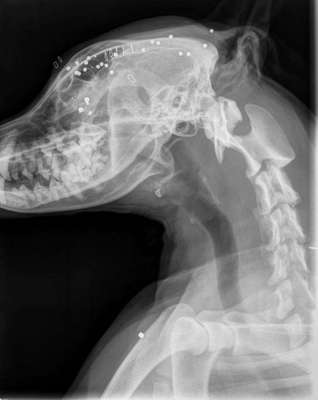

Wenn dein Hund weg ist und er am nächsten Tag vor der Tür steht. Erstmal denke ich wird jeder sowas von froh sein, wenn der Freund nach langem suchen wieder da ist. Was ist aber, wenn er schwer verletzt ist und der Tierarzt dir sagt das es eine Schußverletzung ist und es abzuwarten ist ob er es überlebt. Einer Bekannten ist es so ergangen, die Hündin ist mit ihrem Freund entwischt und stand am nächsten Tag vor der Tür. In einer OP wurde das Auge entfernt und jede Menge Blei entfernt. Es bleibt abzuwarten, ob die Hündin es überlebt, denn das Blei konnte nicht komplett entfernt werden. Eine Bleivergiftung ist tötlich. Was würdet ihr tun? Es hinnehmen oder dagegen angehen? Die Hündin hat sich nicht für Wild interessiert. Der Jäger hat genau ins Auge geschossen und ihr Rüde der hinter ihr stand hat am Ohr eine Verletzung, diese ist aber zum Glück nicht so schlimm. Ein Jäger hat leider sehr wohl das Recht zu schießen, allerdings als letzte Instanz und muß es auch auf einem Formblatt festhalten. Ich finde es widerlich und abgrundtief traurig, das ein Mensch zu so etwas fähig ist. Denn letztendlich entscheidet er als Jäger.

Leider gibt es schlechte Nachrichten..die Maus muß morgen nochmals operiert werden, da sie noch zu viel Blei im Körper hat und die Blutwerte dementsprechend sehr schlecht sind. Ich hoffe sehr auf Besserung und wünsche nur das Beste...